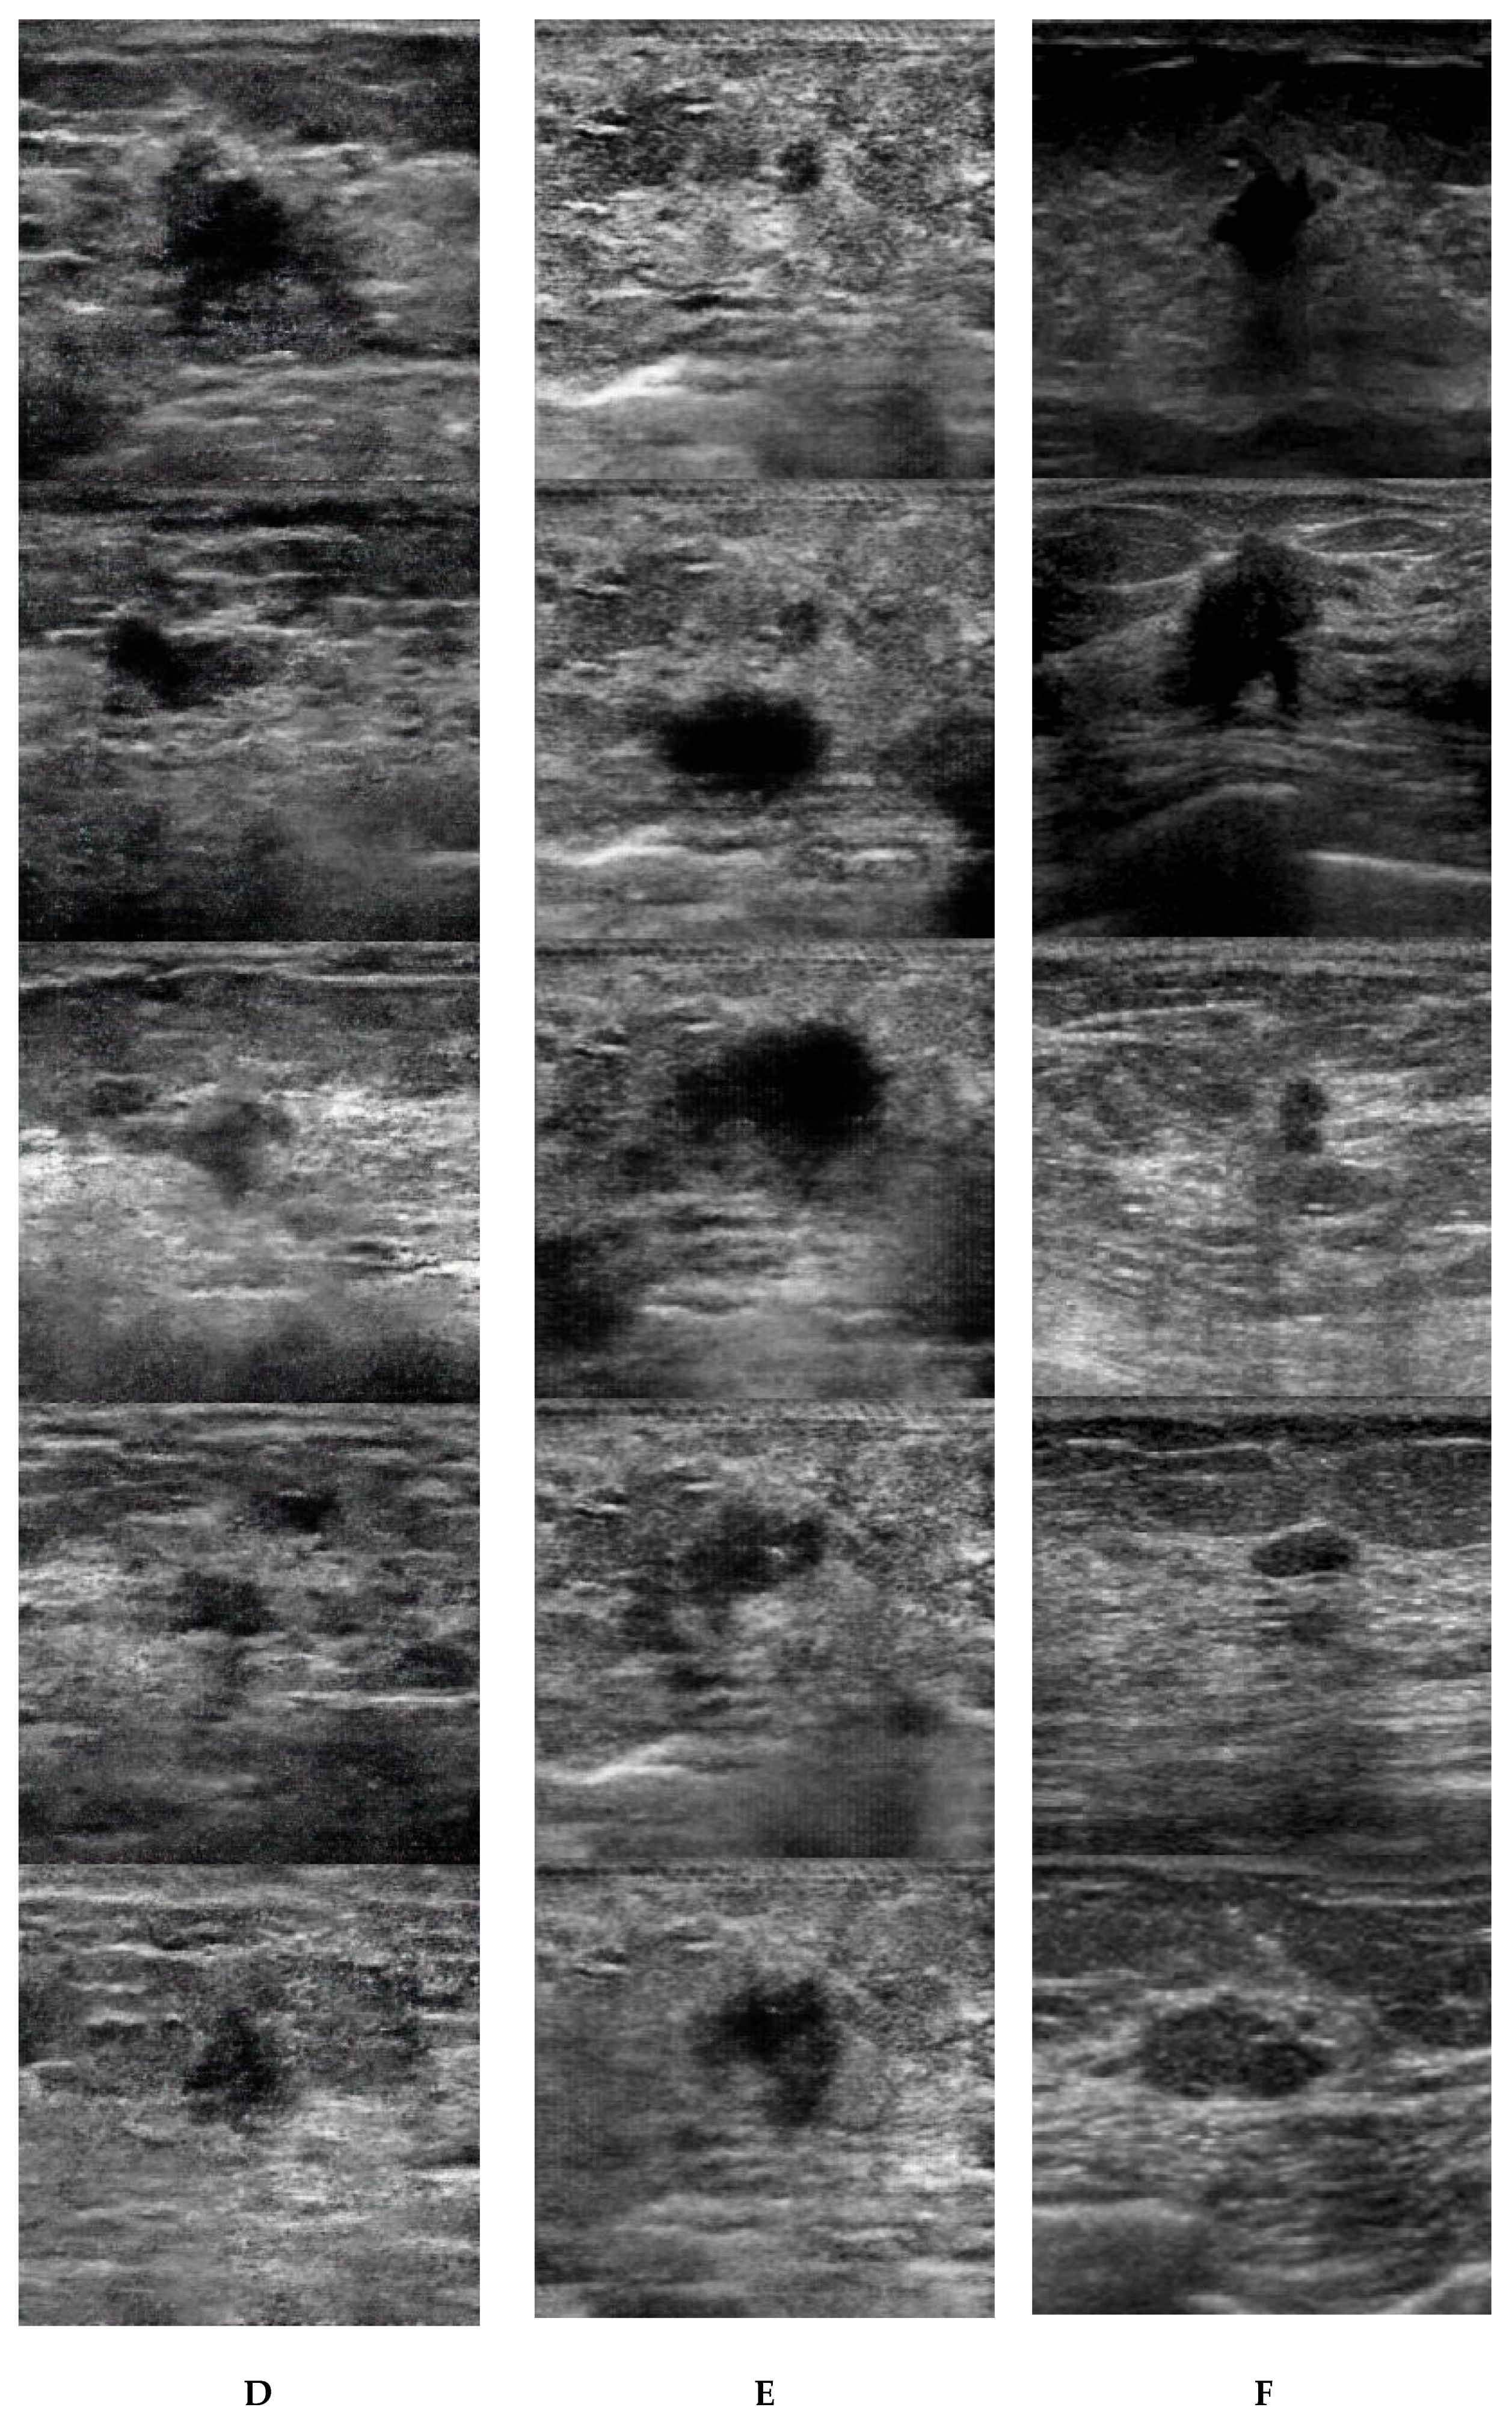

3. Results